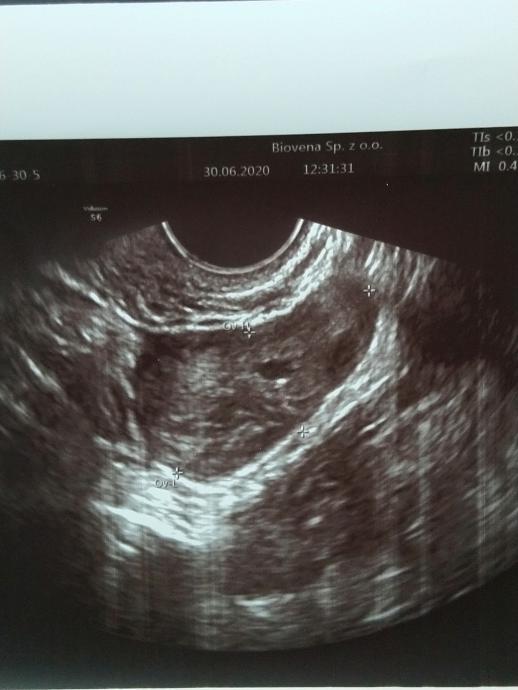

Czy wiecie co to możne być za organ i ciemna plama w nim? Zdjęcie robione 30 dnia cyklu (ten wtorek). Lekarz powiedział mi, że mam cienkie endometrium i nic poza tym.

Czy to może być pęcherzyk w jajniku, czy jakaś torbiel w macicy?